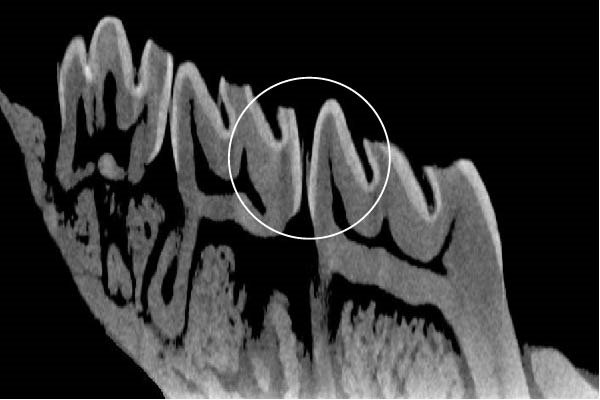

Figure 3 shows the micro‐CT images of OTM in some subgroups.

Figure 3Micro‐CT analysis of OTM after 21 and 40 days: (A) orthodontic treatment/CE injection/stress (chronic); (B) orthodontic treatment/CE injection/stress (acute); (C) orthodontic treatment/stress (chronic); (D) orthodontic treatment/stress (acute); (E) no orthodontic treatment/CE injection/stress (chronic); (F) no orthodontic treatment/CE injection/stress (acute); (G) no orthodontic treatment/no drug (chronic); (H) no orthodontic treatment/no drug (acute).(A)(B)(C)(D)(E)(F)(G)(H)